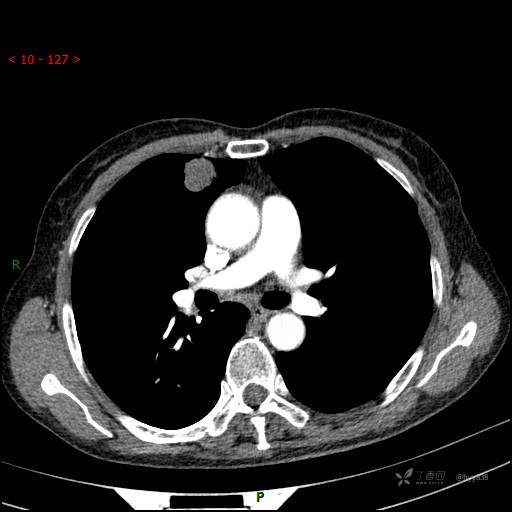

CT值